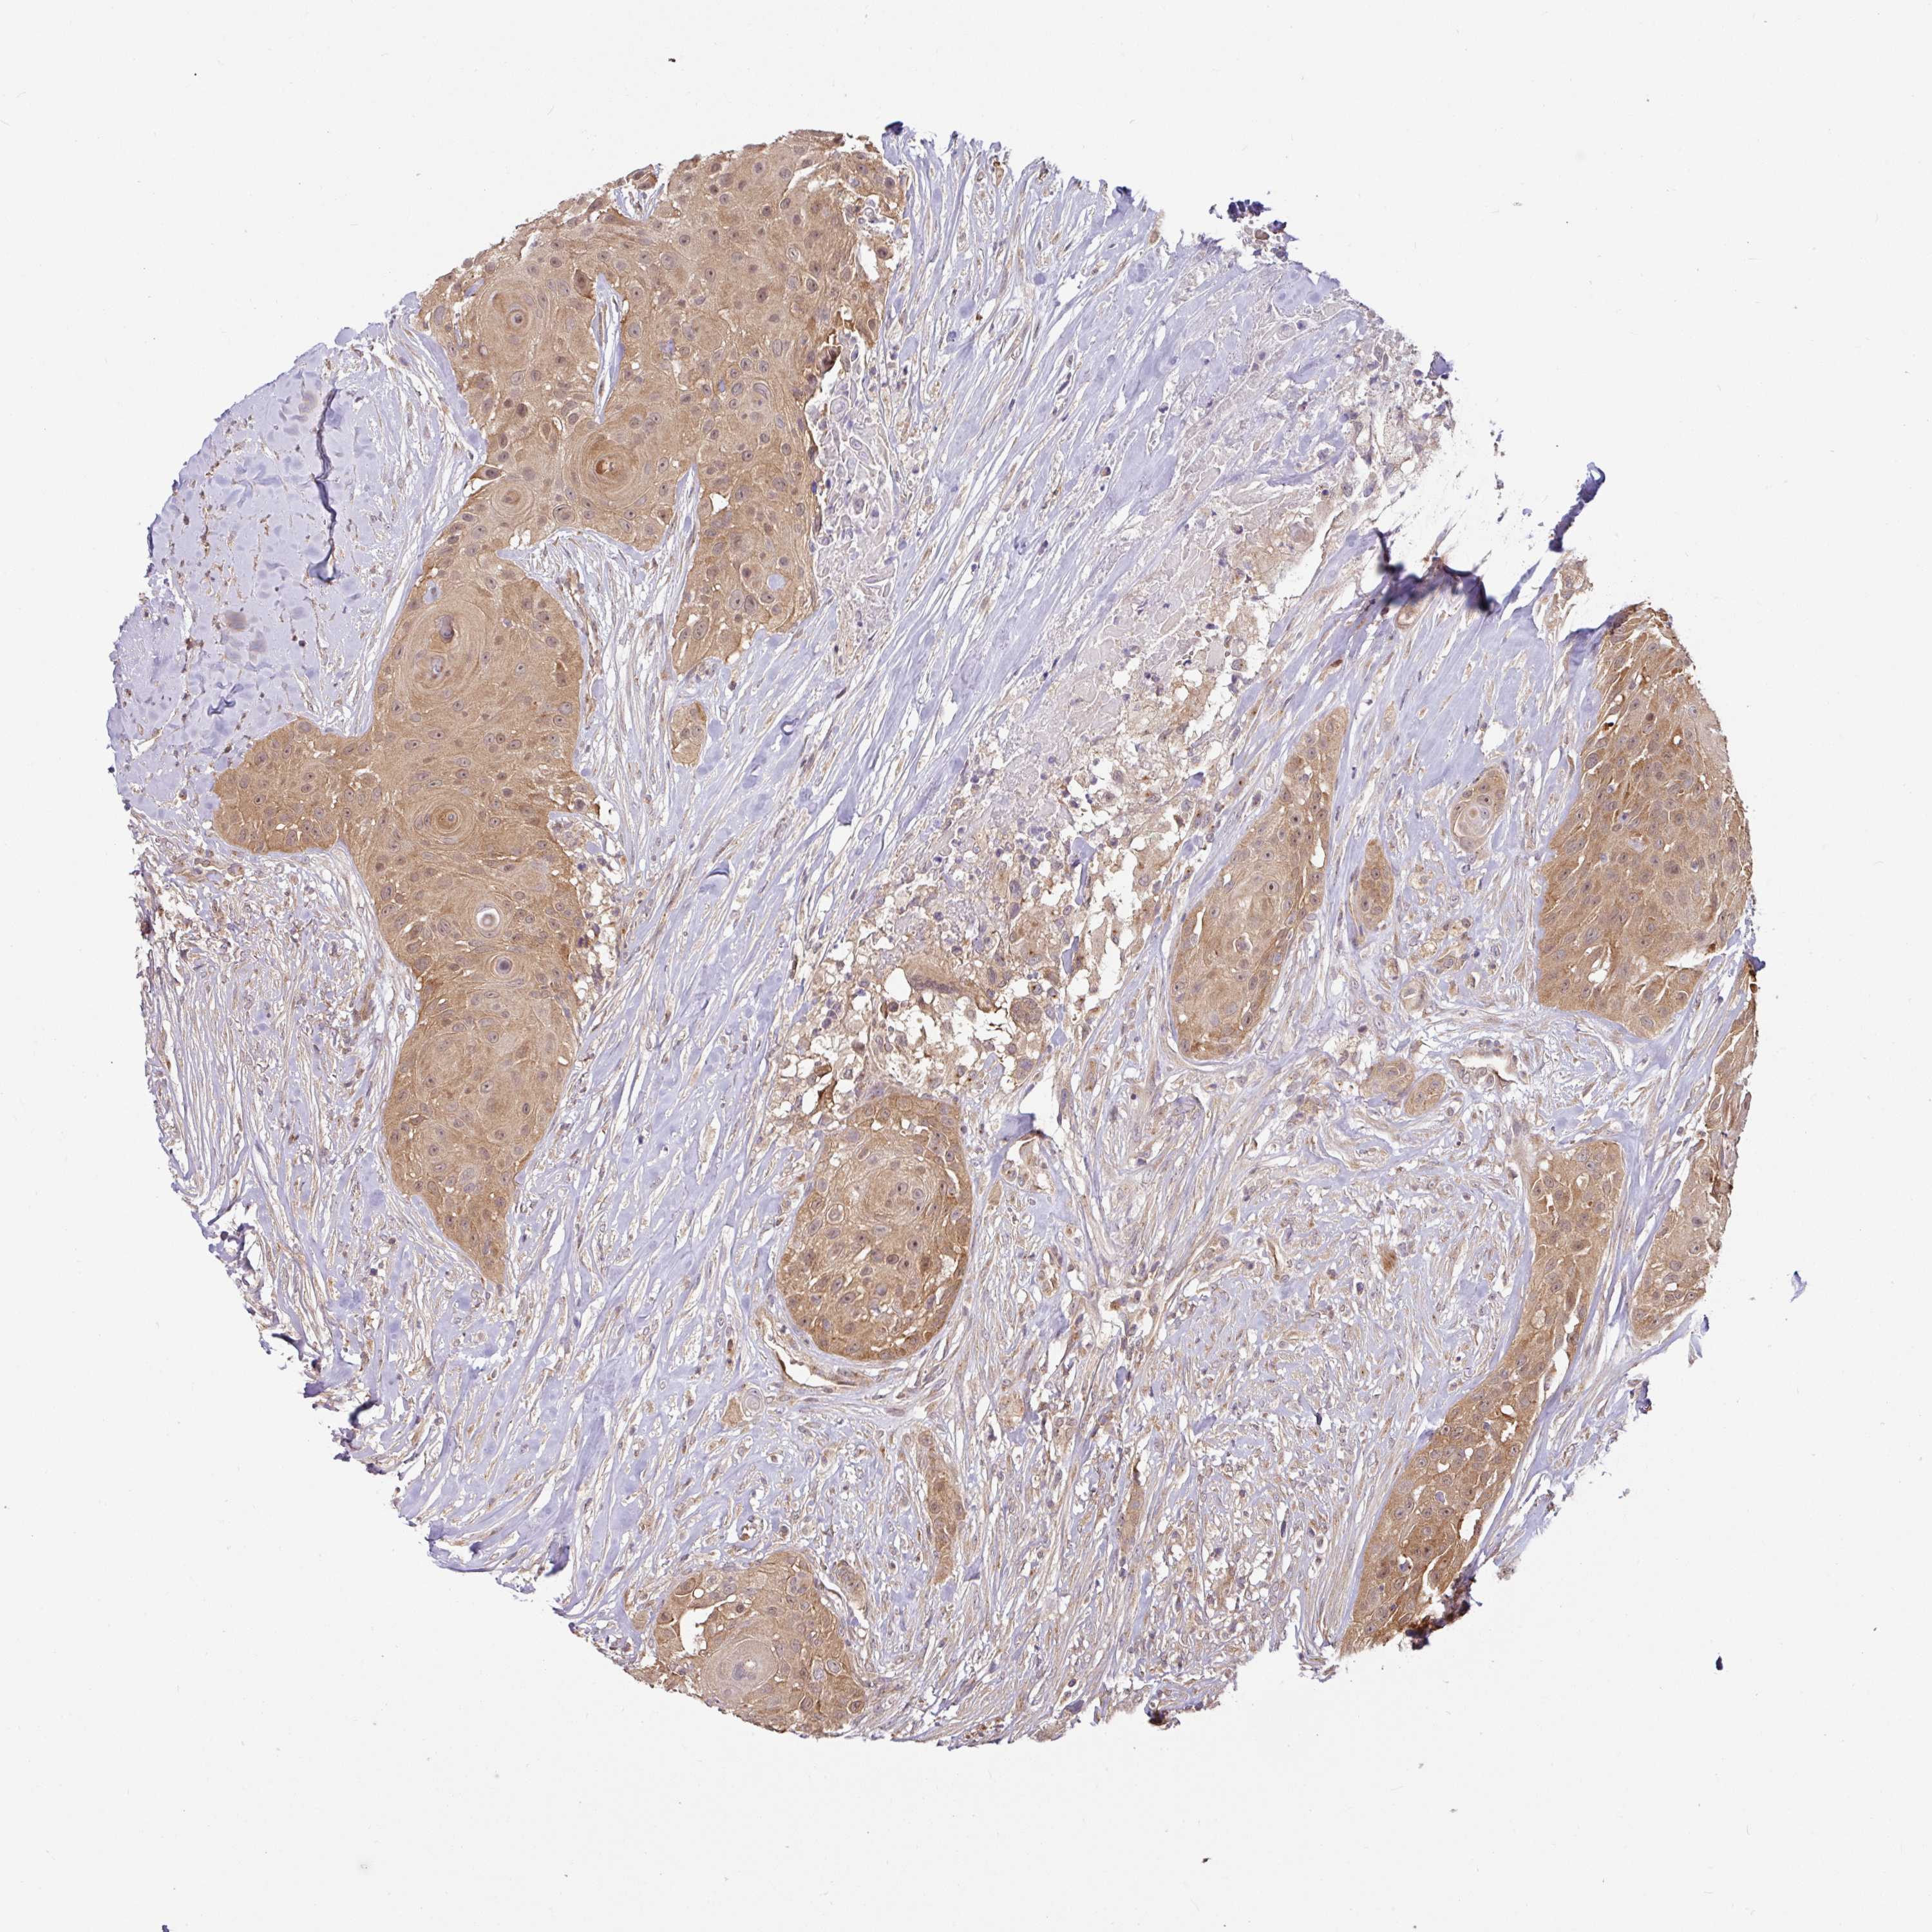

HEAD AND NECK CANCER - Protein expressioni

A mouse-over function shows sample information and annotation data. Click on an image to view it in a full screen mode. Samples can be filtered based on level of antibody staining by selecting one or several of the following categories: high, medium, low and not detected. The assay and annotation is described here.

Antibody stainingi

Antibody staining in the annotated cell types in the current human tissue is reported as not detected, low, medium, or high, based on conventional immunohistochemistry profiling in selected tissues. This score is based on the combination of the staining intensity and fraction of stained cells.

Each image is clickable and will lead to virtual microscopy that enables deeper exploration of all samples and also displays staining intensity scores, fraction scores and subcellular localization as well as patient and tissue information for each sample.

Antibody HPA049911

Antibody CAB010161

Staining

High

Medium

Low

Not detected

Intensity

Strong

Moderate

Weak

Negative

Quantity

>75%

75%-25%

<25%

None

Location

Nuclear

Cytoplasmic/membranous

Cytoplasmic/membranous,nuclear

Squamous cell carcinoma, NOS